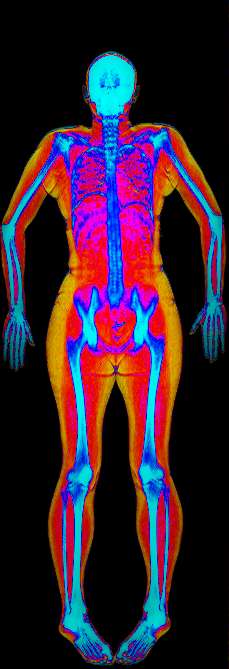

Bone Density Z-score

The Z-score shows how your bone density compares to the bone densities of others who are the same age, gender, and ethnicity.

• Zone 1: Very common, about 68 out of 100 people your age have Z-scores in this range.

• Zone 2: Less Common, about 28 out of 100 people your age fall in this range.

• Zone 3: Very Rare, about 4 out of 100 people your age have Z-scores within this range.

Your Z-Score is 0

Z-scores for bone density compare an individual's bone density to the average bone density of people of the same age, sex, and body size. A Z-score of 0 indicates that the bone density is exactly average. Scores below -2.0 may suggest a higher risk of bone fractures or underlying medical conditions affecting bone health.

Bone Density T-score

The T-score shows how your bone density compares to the optimal peak bone density of a 25 year old Female.

The World Health Organization (WHO) defines osteoporosis and osteopenia based on T-scores:

• Normal bone density: T-score above -1 SD

• Osteopenia (low bone density): T-score between -1 and -2.5 SD

• Osteoporosis: T-score of -2.5 SD or lower

T-Score is 0.2. You have Normal Bone Density

Please Note: Full-body bone density scans provide an overall indication of bone health, but for a definitive osteoporosis diagnosis, please arrange separate scans of the hip and spine.

It's important to note that T-scores alone do not determine fracture risk; other factors such as age, sex, medical history, and lifestyle also play a role. Additionally, a T-score is just one component of a comprehensive assessment for osteoporosis and fracture risk. Interpretation of T-scores should be done in consultation with a healthcare professional.

Whole Body Bone Density

Your bone mineral density is 1.118g/cm²

Area (cm²) BMC (g) BMD (g/cm²) T-Score Z-Score

Total 2035.67 2275.12 1.118 0.2 0